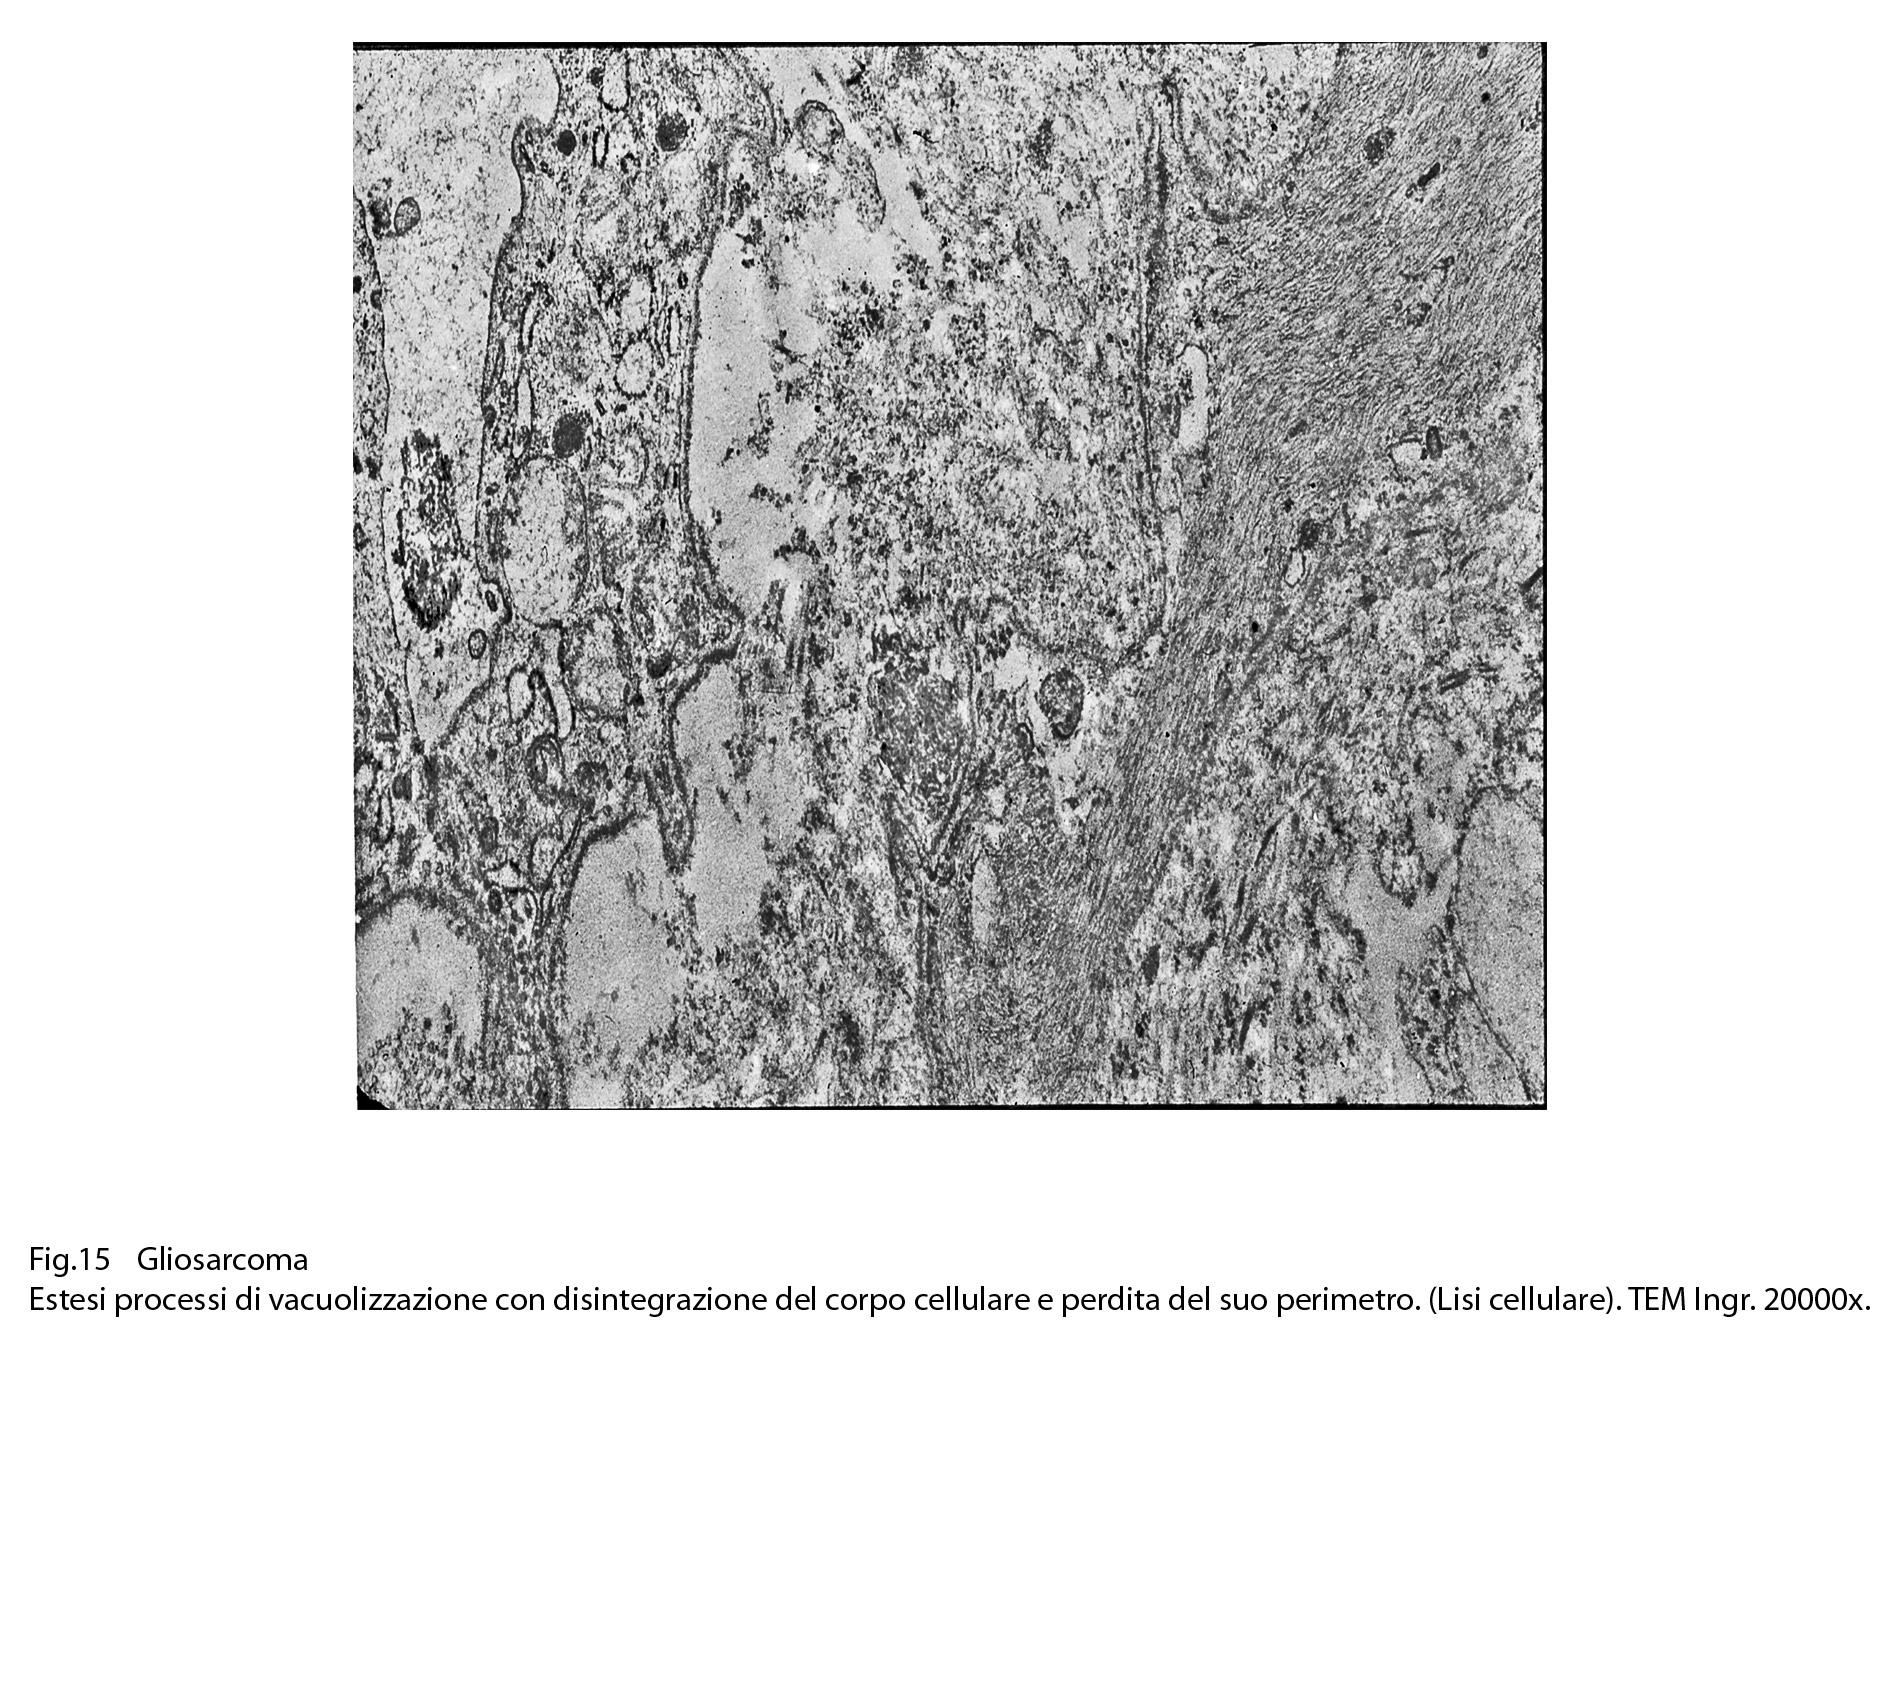

Fig.15